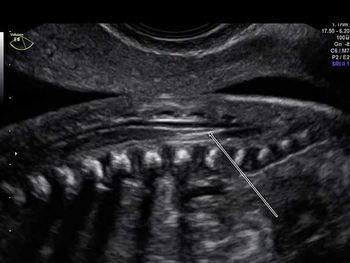

Challenge your anatomy skills: Can you identify the spinal structure?